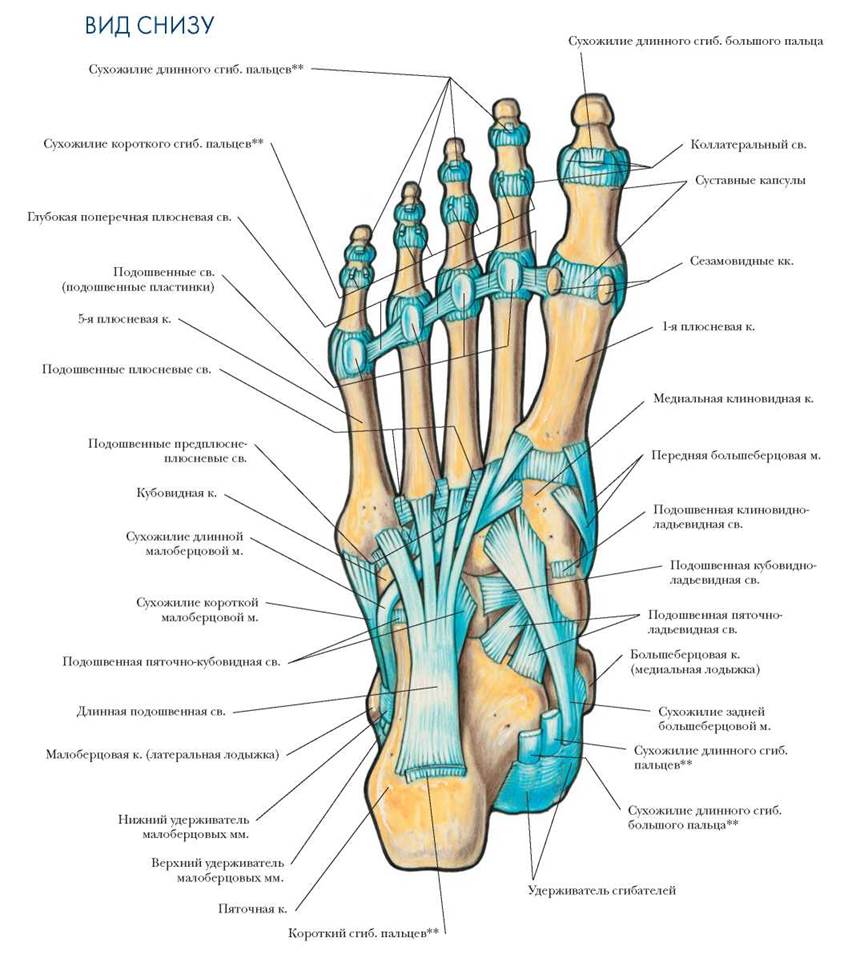

Анатомические фото голеностопного сустава и его суставных поверхностей